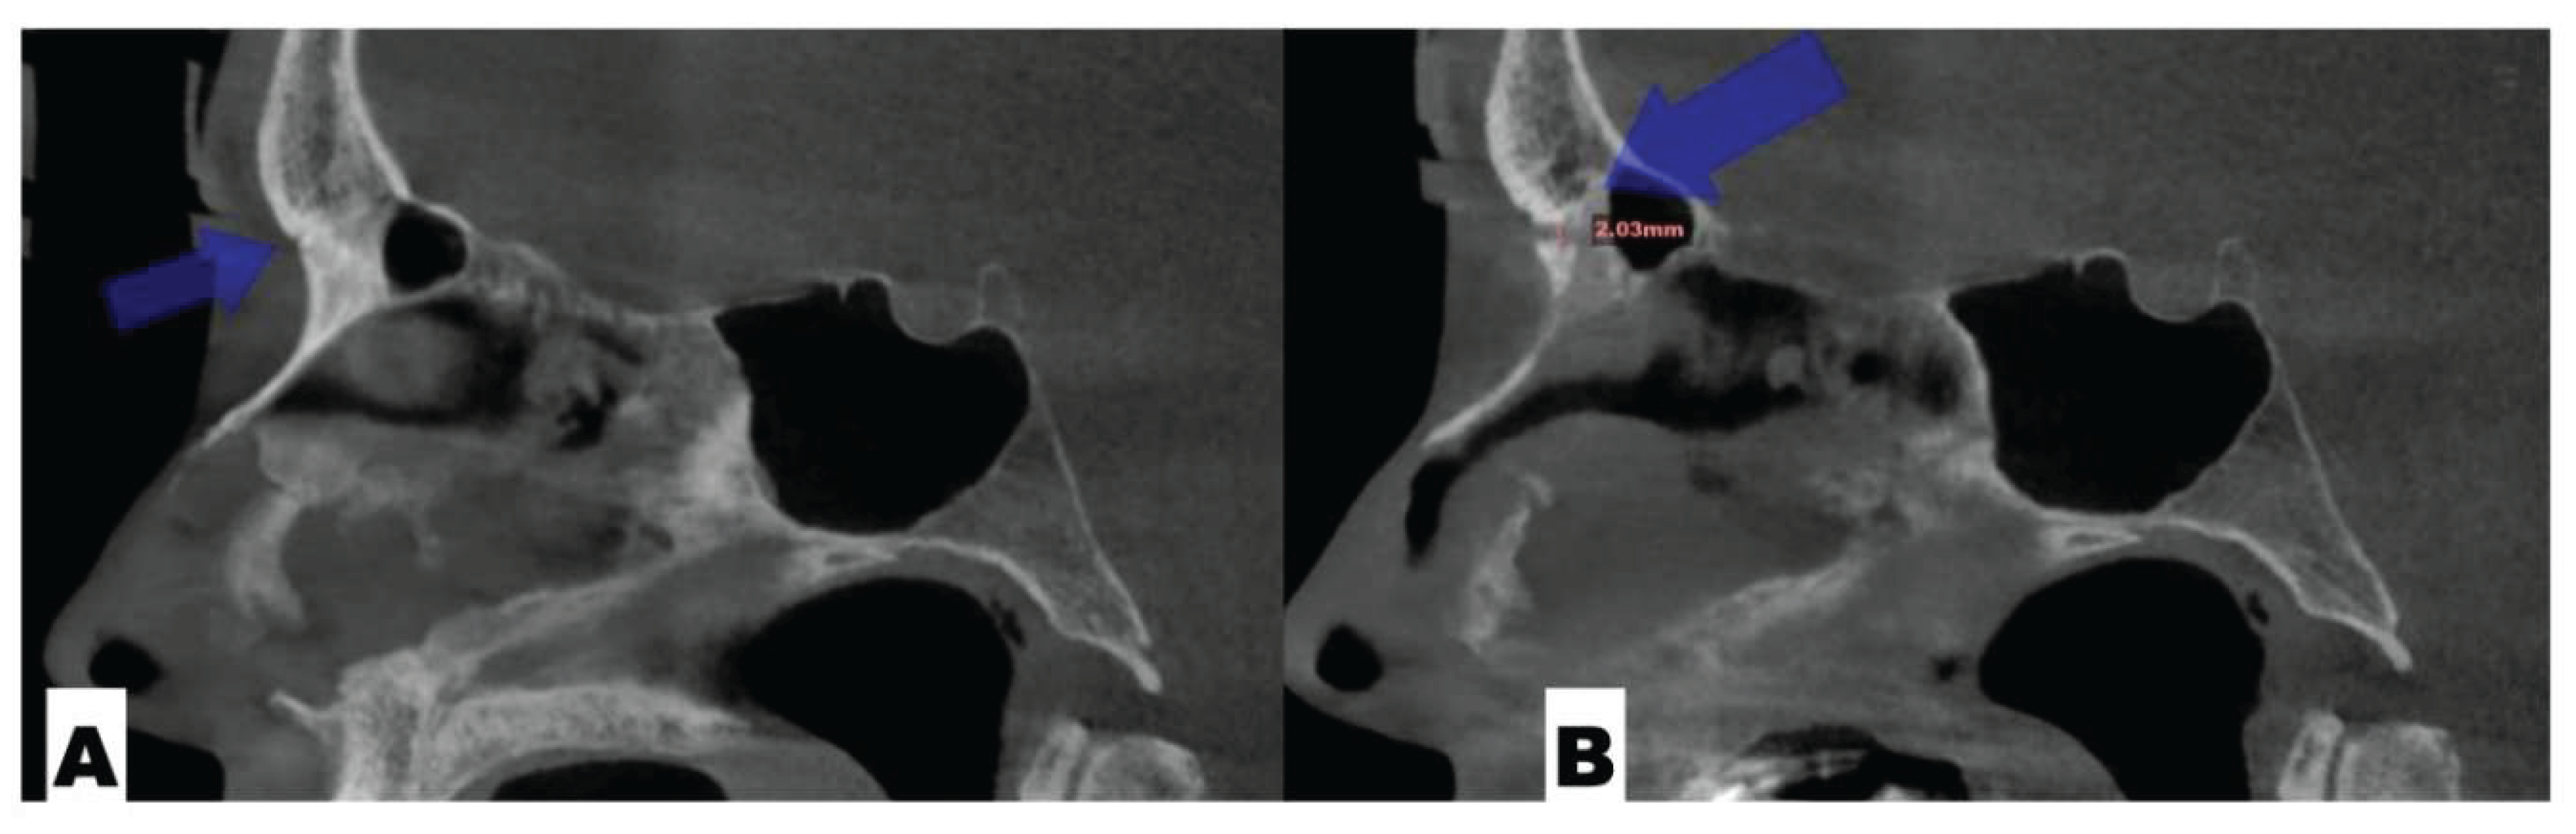

Background: While mini-screw-assisted rapid palatal expansion (MARPE) is effective for correcting maxillary transverse deficiency in adults, perimaxillary suture disarticulation—particularly at the pterygomaxillary junction—can be inconsistent. This study evaluates skeletal and dentoalveolar outcomes of a novel 3D-guided midpalatal piezocorticotomy-assisted MARPE protocol, focusing on expansion symmetry and pre-existing asymmetries. Methods: Three adult patients were retrospectively analyzed after treatment with 3D-guided midpalatal piezocorticotomy-assisted MARPE expansion and one with non-guided midpapalatal piezocorticotomy and MARPE expansion. Surgical guides were digitally designed using CBCT data to align with the nasal septum orientation in multiple planes. Perimaxillary suture disarticulation was measured pre- and post-expansion, and dentoalveolar changes were evaluated. Post-expansion asymmetries were addressed using directly printed aligners. Results: Complete midpalatal suture separation (mean 8.48 mm), involving both anterior and posterior nasal spine regions, was achieved in one patient. Bilateral pterygomaxillary disarticulation averaged 1.06–1.23 mm, resulting in forward–outward rotation of the nasomaxillary complex. Additional separation occurred at the frontonasal (2.03 mm) and vomeromaxillary (1–2 mm) sutures, with no significant changes in orbital or peri-orbital sutures. One patient presented with pre-existing dentoalveolar asymmetry, which intensified the perceived post-expansion imbalance but was successfully corrected with directly printed aligners. In the second case, 5.6 mm of suture separation resulted in a limited lateral nasal width increase (<1.5 mm), while maxillary base expansion exceeded 6 mm. A significant canine plane cant (1.2 mm) and divergent axial inclinations of the maxillary central incisors relative to the palatal plane were also observed. In the second case, a non-impactful palatal bone fracture with asymmetric displacement of the left palatine fragment was documented. After 16 months of aligner therapy, all cases exhibited favorable remodeling of the palatal structures, midpalatal suture, and alveolar processes, accompanied by improved dental alignment, occlusal plane symmetry, and mandibular dentoalveolar adaptation. The dento-alveolar expansion achieved in the third case over the course of 16 months of treatment was approximated at 4 mm. The fourth case showed consistent improvement with direct printed aligners after MARPE midpalatal diasrticulation of 11 mm after experiencing minor bone fracture. Conclusions: Human skulls exhibit considerable variability between the left and right sides, which can influence spatial balance. Pre-existing cranial asymmetries appear to be the primary contributors to asymmetry following MARPE treatment. Careful evaluation of dentoalveolar discrepancies and axial tooth inclinations is essential for preventing and managing potential asymmetric dental arch outcomes during the post-expansion phase. Although peri-maxillary bone fractures are relatively uncommon, their occurrence is influenced by multiple factors. Adjunctive techniques, such as 3D-guided midpalatal piezocorticotomy, show promise in significantly lowering the risk of intra-expansion peri-maxillary fractures.

| Frontonasal | 2.03 mm |